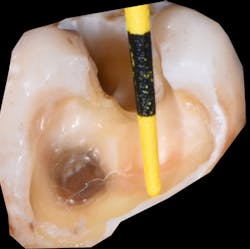

Figure 1: Proximal boxes in Class II restorations can be several millimeters deep.

Historically, composite resins have been classified primarily based on the particle size in the filler: macrofill, microfill, hybrid, microhybrid, nanofill, and nanohybrid. And, depending on the amount of filler load, there are the standard “packable” or normal viscosity resin and flowable resins that are more fluid in nature. Typically, when placing resin into a cavity preparation, especially in Class I and Class II preparations, careful attention is needed in the overall placement, as many of these preparations can be several millimeters in depth (figure 1) and too deep for sufficient penetration of light (figure 2) and proper curing of the resin.